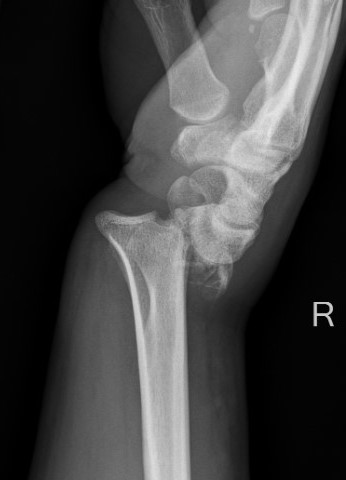

Xray

Dorsal radiocarpal dislocation with dorsal rim fracture

Dorsal radiocarpal dislocation with radial styloid fracture